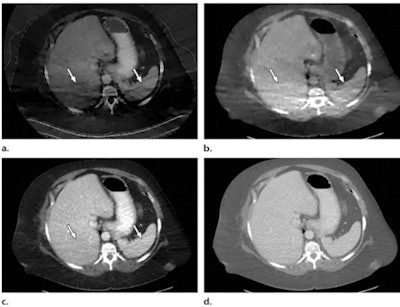

Photon starvation in a large patient. Axial portovenous-phase abdominopelvic CT was performed in a 242-lb patient using rapid kilovolt peak (kVp) switching DECT. (a) Material density iodine image shows dark bands of artifact (arrows) across the liver and spleen. (b) On an MD-water image, the streaks appear as bright bands (arrows). (c) On a 65 kilo-electron volt (keV) image, the artifacts are much less apparent (arrows). (d) On a 140 kVp-equivalent image, the artifacts are not visualized. Images and caption courtesy of the RSNA.There's no doubt that DECT is a promising technology, but radiologists must understand it to use it effectively, according to the team.